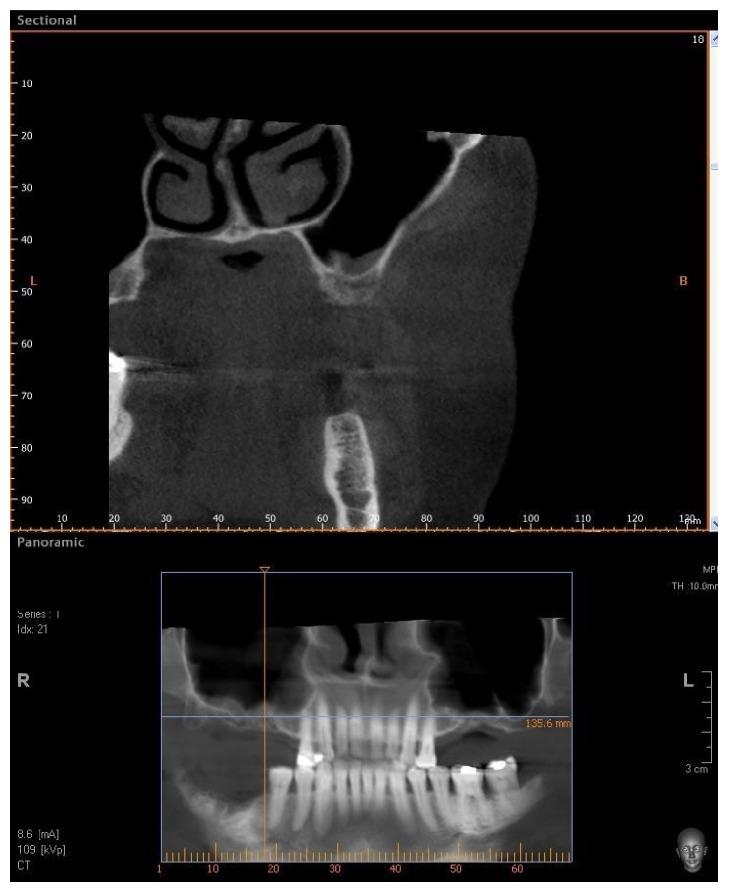

. One of the most problematic regions for endosseous implants is the posterior maxilla, not only having poor bone density, but also lacking adequate vertical height as a result of sinus pneumatization. The purpose of the present study was a radiologic, histological, and histomorphometrical evaluation, in humans, of specimens retrieved from sinuses augmented with decellularized bovine compact particles, after a healing period of 6 months. . Four patients, with atrophic resorbed maxillas, underwent a sinus lift augmentation with decellularized bovine compact bone from bovine femur. The size of the particles used was 0.25-1 mm. A total of four grafts and 5 biopsies were retrieved and processed to obtain thin ground sections with the Precise 1 Automated System. . The mean volume after graft elevation calculated for each of the 4 patients was 2106 mm in the immediate postoperative period (5-7 days), ranging from 1408.8 to 2946.4 mm. In the late postoperative period (6 months) it was 2053 mm, ranging from 1339.9 to 2808.9 mm. Histomorphometry showed that newly formed bone was 36 ± 1.6% and marrow spaces were 34 ± 1.6%, while the residual graft material was 35 ± 1.4%. . In conclusion, based on the outcome of the present study, Re-Bone® can be used with success in sinus augmentation procedures and 6 months are considered an adequate time for maturation before implant placement.

对于骨内种植体而言,最具问题的区域之一是上颌后牙区,该区域不仅骨密度差,而且由于鼻窦气化导致垂直高度不足。本研究的目的是对在6个月愈合期后从用脱细胞牛致密颗粒增强的鼻窦中取出的人体标本进行放射学、组织学和组织形态计量学评估。4例上颌萎缩吸收患者接受了用牛股骨脱细胞致密骨进行的鼻窦提升增强术。所用颗粒大小为0.25 - 1毫米。共取出4块移植物和5份活检标本,并用Precise 1自动系统处理以获得薄磨片。4例患者术后即刻(5 - 7天)计算的移植物提升后平均体积为2106立方毫米,范围为1408.8至2946.4立方毫米。术后晚期(6个月)为2053立方毫米,范围为1339.9至2808.9立方毫米。组织形态计量学显示,新形成的骨为36±1.6%,骨髓腔为34±1.6%,而剩余移植物材料为35±1.4%。总之,基于本研究结果,Re - Bone®可成功用于鼻窦增强手术,6个月被认为是种植体植入前成熟的足够时间。